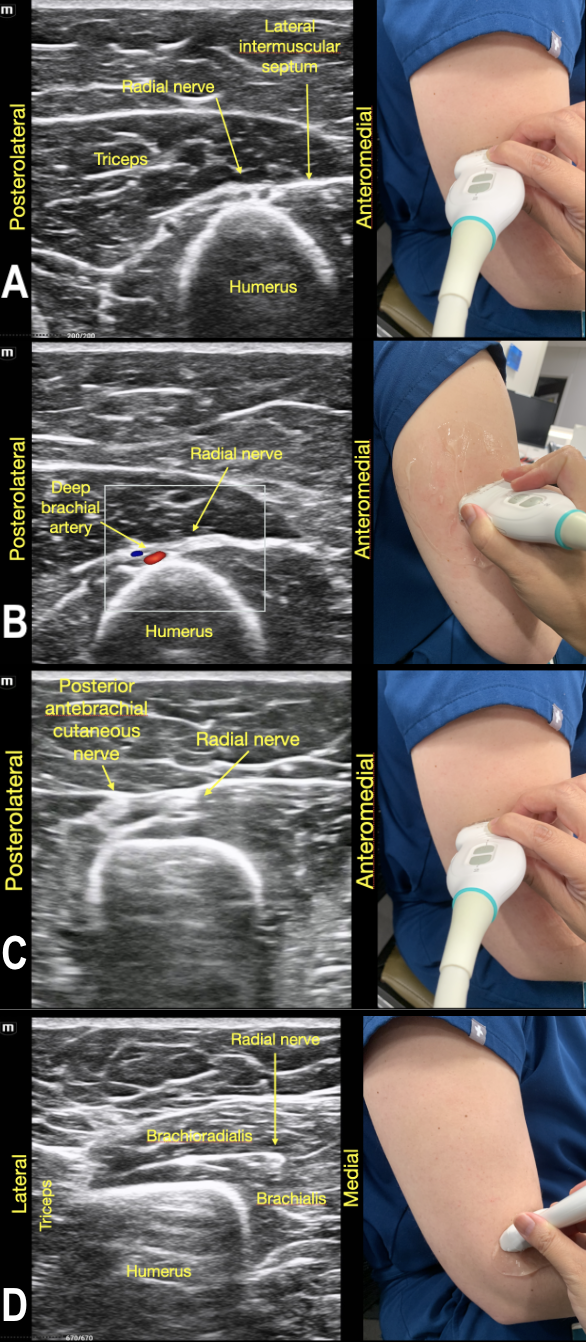

To identify the radial nerve in the mid-humerus position, have the patient in a seated position with the arm extended or held over the abdomen with the elbow flexed. Start with the probe placed transverse across the posterolateral mid-humerus and identify the radial nerve as a hyperechoic honeycombed structure lying directly on top of the humerus. At this point the radial nerve lies within the spiral groove and is also seen adjacent to the deep brachial artery. (Figure 7A)

As the probe is moved distally along the spiral groove, the posterior cutaneous nerve of the forearm can be seen branching from the radial nerve just prior to the lateral intermuscular septum (Figure 7D). In Video Clip 1, the radial nerve passes from the triceps into the biceps through the linear echogenic lateral intermuscular septum, which is a hyperechoic connective tissue layer separating the dorsal and anterior compartment of the arm.13

As the radial nerve is traced further distally, it can be seen leaving the spiral groove and wrapping around the anterior arm as it moves medially in between the brachioradialis and the brachialis muscle (Video Clip 2). The probe at this point is 3-4 cm above the elbow crease. This is the level that is blocked in the supracondylar UGRA. (Figure 5) A block at the supracondylar level will anesthetize the superficial and deep branch of the radial nerve as this branchpoint occurs distal to the elbow crease at the cubital fossa. The deep branch of the radial nerve continues between the brachioradialis and brachialis muscles, then passes through the supinator muscle emerging as the posterior interosseous nerve (PIN). The PIN provides motor innervation for the extensor muscles in the posterior compartment of the forearm as well as some sensory fibers to the dorsal wrist capsule. The superficial branch runs deep to the brachioradialis muscle then runs along the radial artery into the forearm, crossing over the snuffbox to the dorsum of the hand, and provides sensation to the dorsal hand and digits in the radial distribution.

RadialNerve-Image7 Aug2024.pngFigure 7. The Radial Nerve in its trajectory proximal to distal.